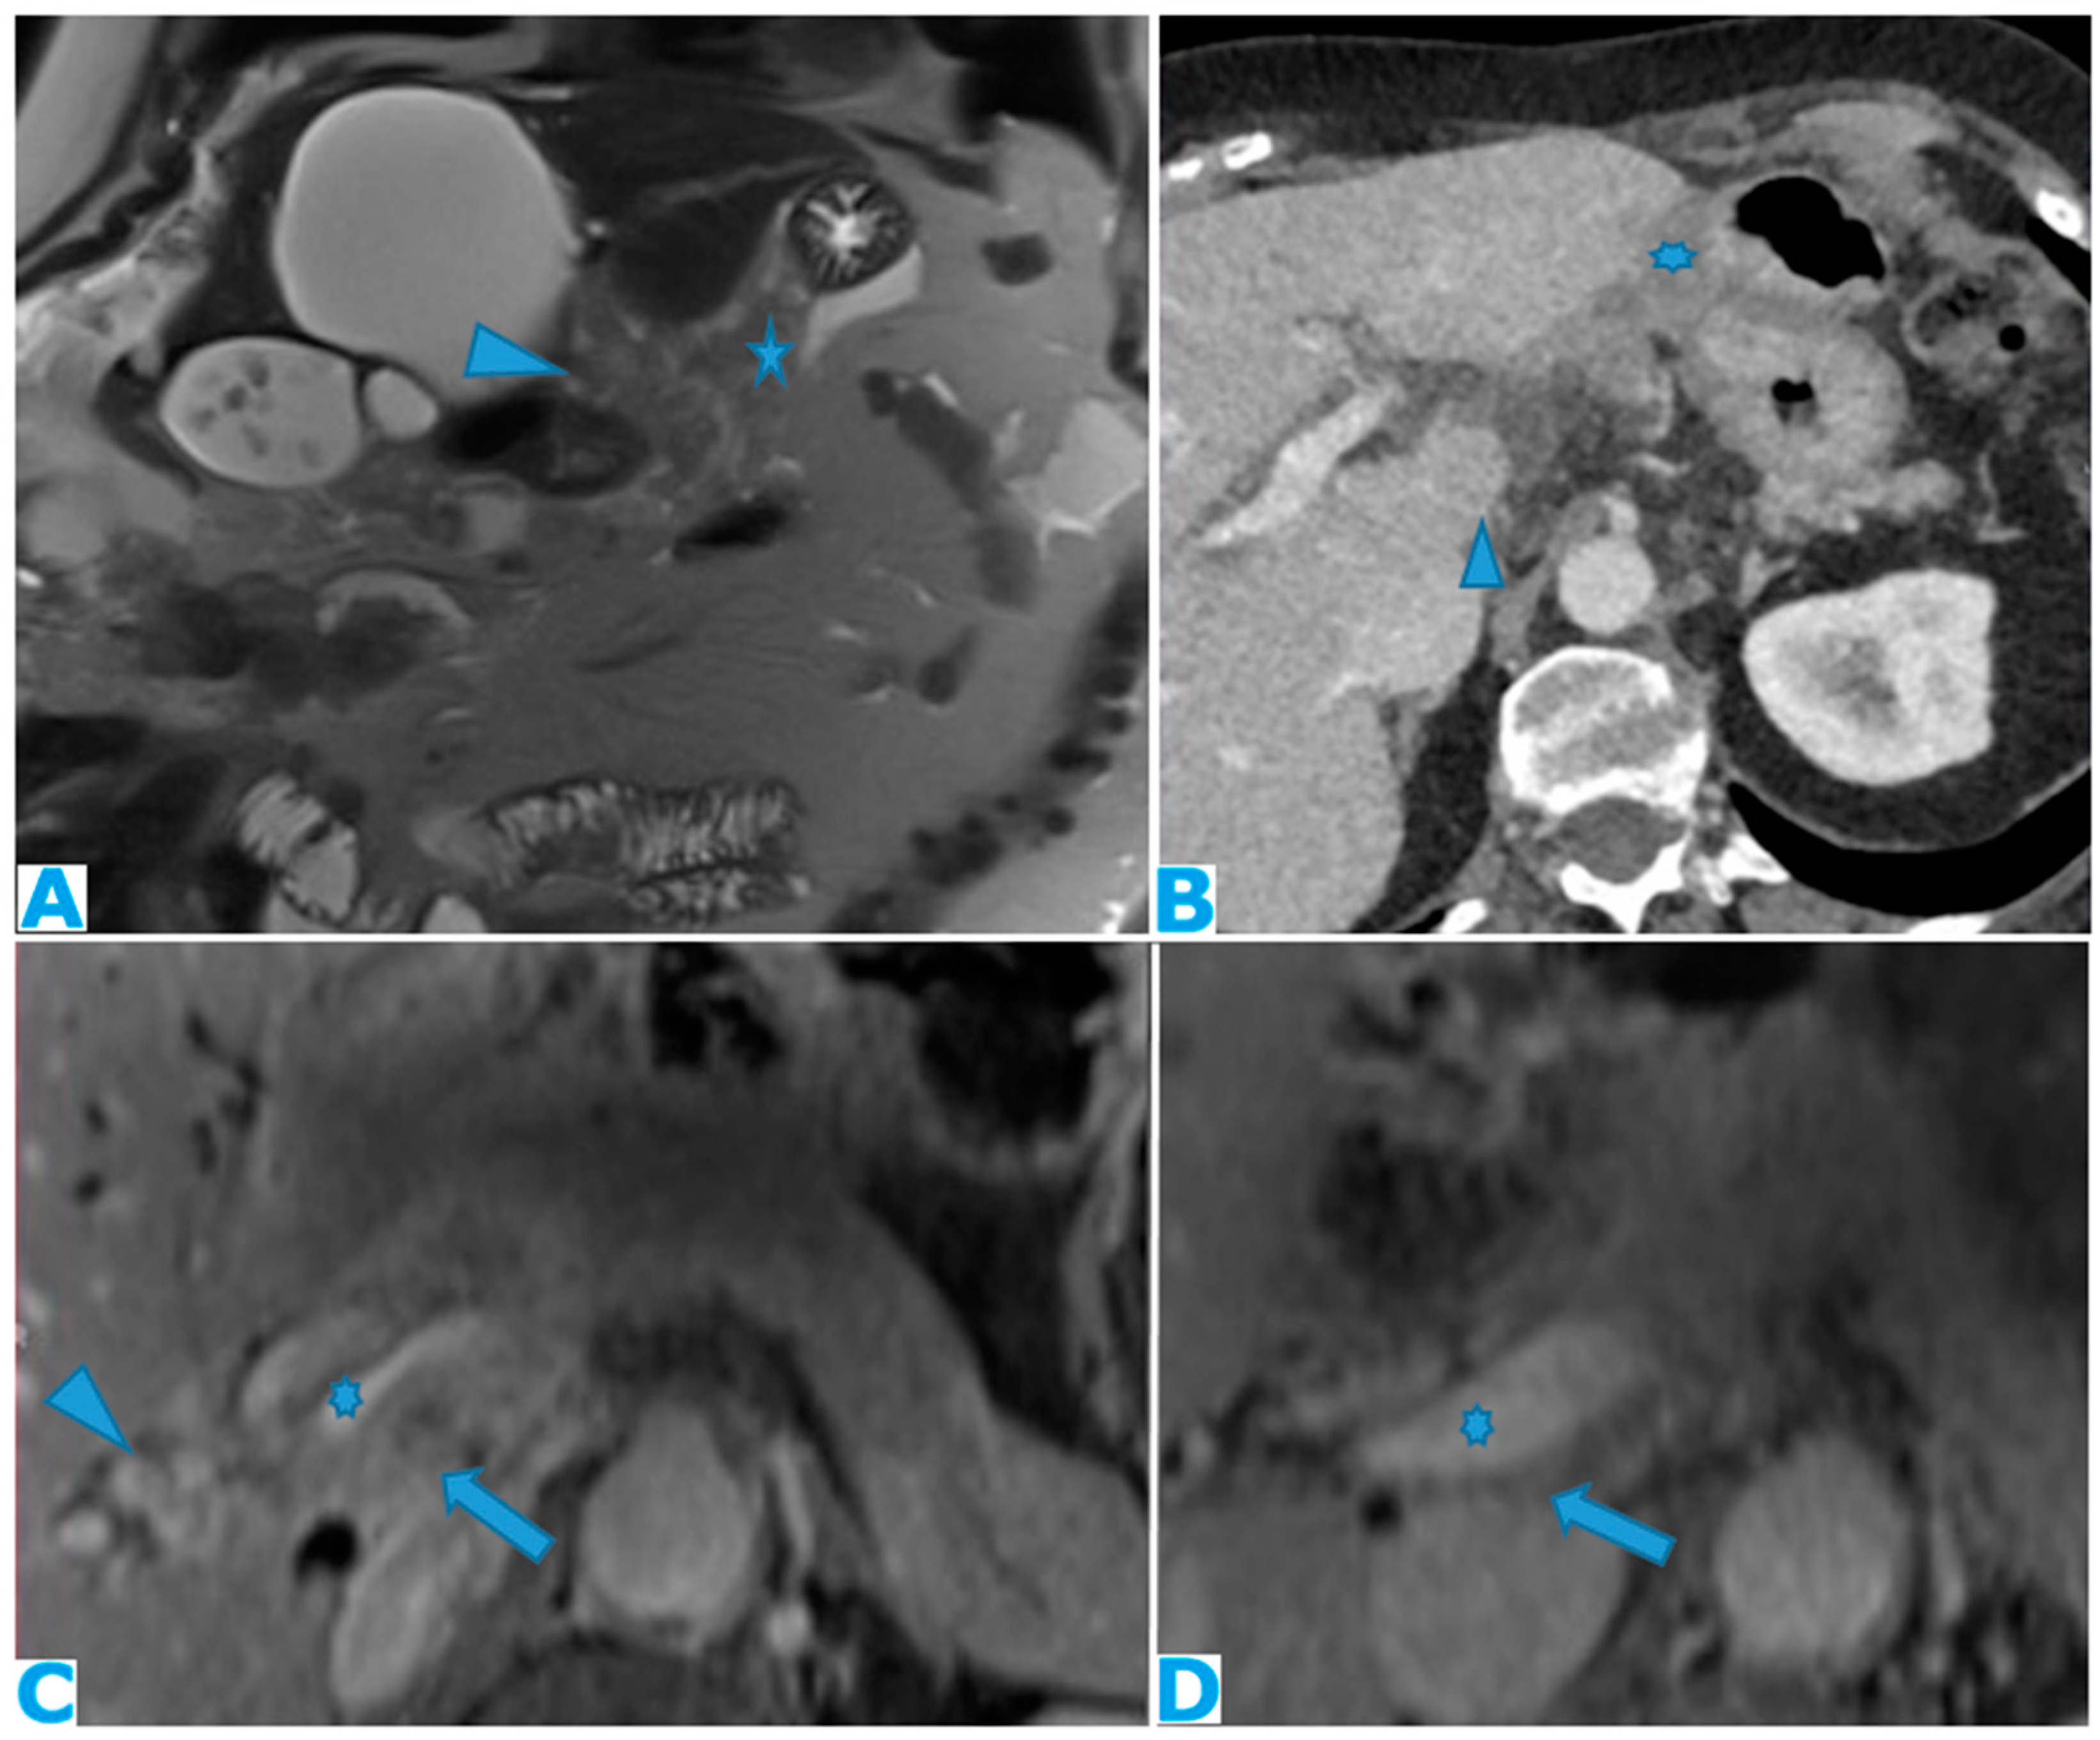

Figure 24.

Axial CE-CT (A), axial T2WI (B), axial CE portal phase FS T1WI (C). PC from endometrial carcinoma: Deposit seeding within the mesenteric leaves.